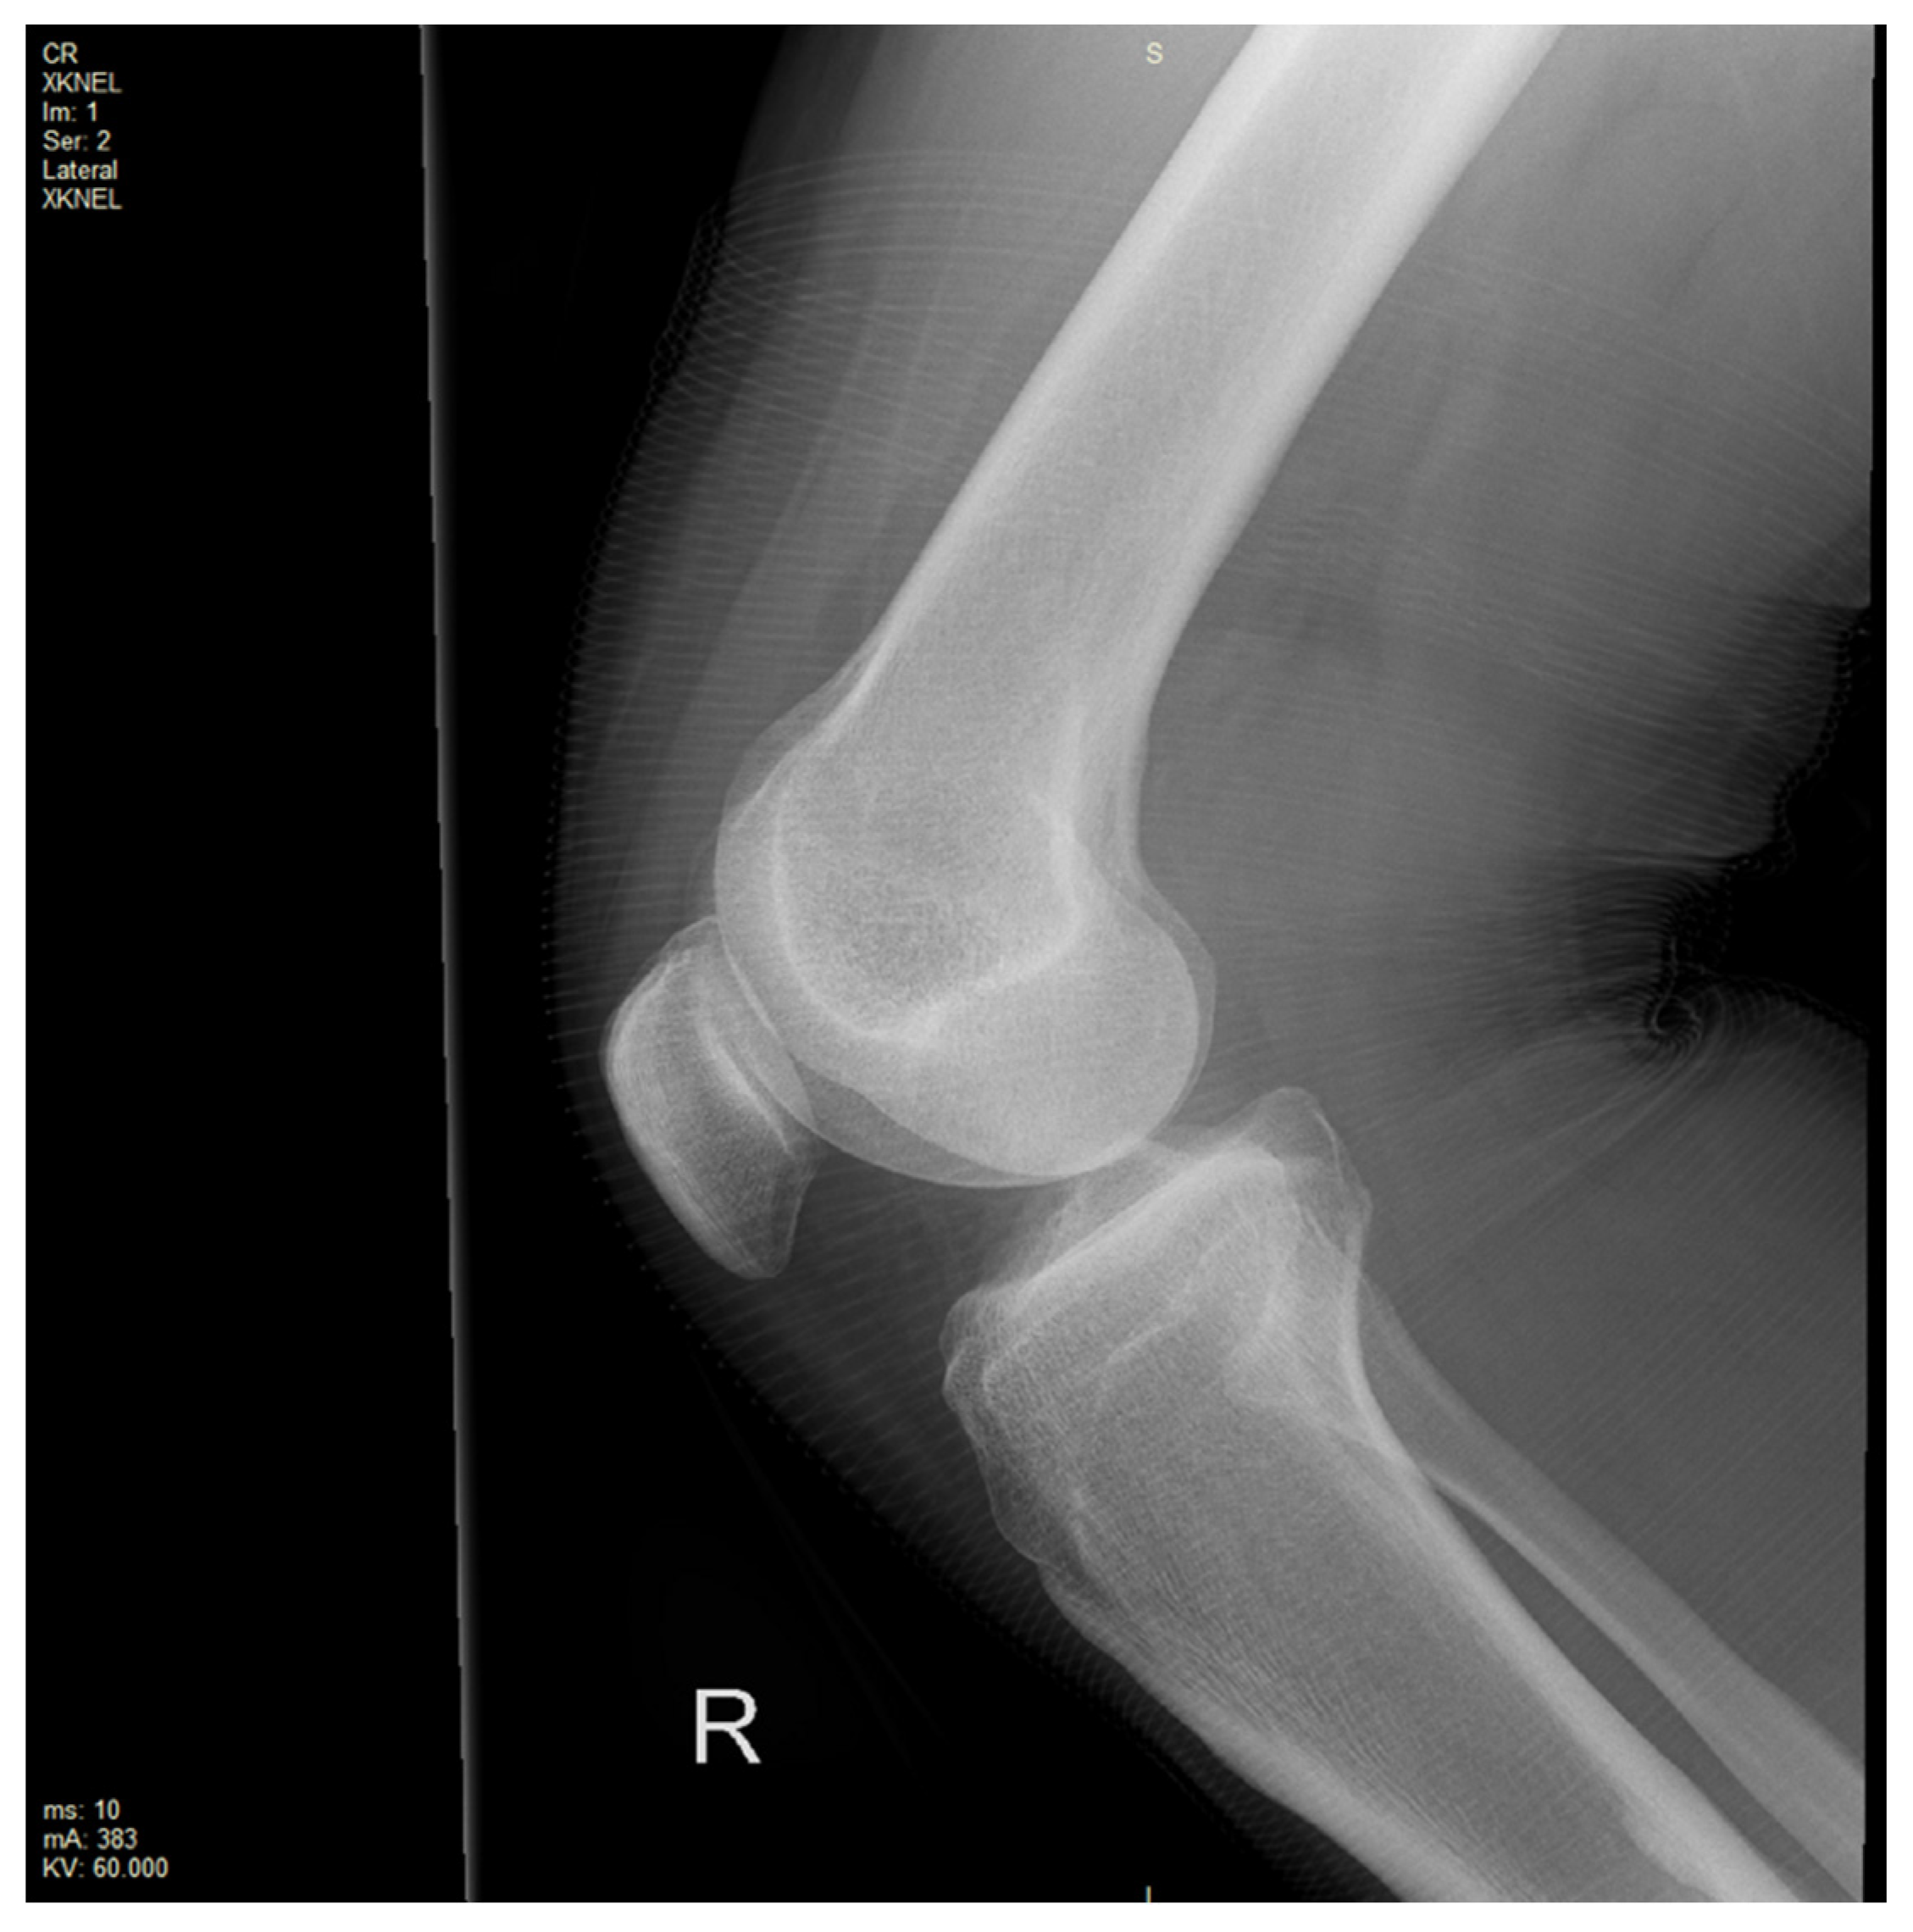

An X-ray of the right knee was initially performed to rule out a bony injury (Figure 1). The X-ray demonstrated marked soft tissue swelling of the knee joint with moderate effusion extending into the supra-patella recess. There was no evidence of acute or recent bony injury. The presence of radiological joint effusion raised suspicion for potential ligamentous or meniscal injuries. Subsequently, a magnetic resonance image (MRI) of the right knee was performed to further characterise the injury. MRI was obtained with a 1.5T Philips Achieva dStream MRI (Philips, Amsterdam, Netherlands) with Release 5.7 software. The routine knee protocol was performed, including sequences as follows: Axial Proton Density T2-weighted Turbo Spin Echo (Axial PD TSE), Proton Density Spectral Attenuated Inversion Recovery (PD SPAIR), Sagittal PD TSE, PD SPAIR, Coronal PD TSE, PD SPAIR (Figure 2a,b and Figure 3a,b).

Figure 1. X-ray of the right knee with a soft tissue shadow extending into the supra-patellar recess.